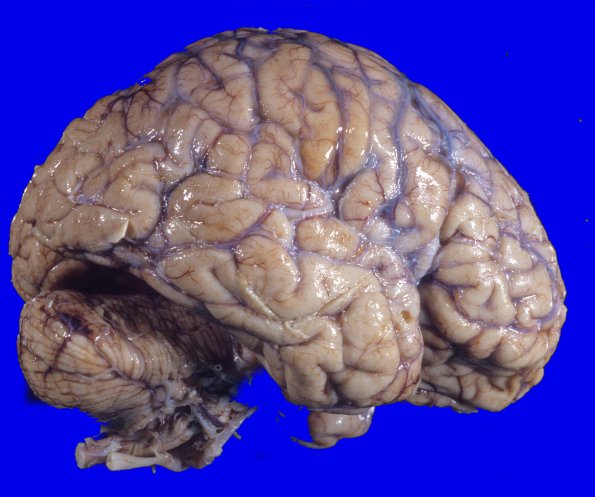

At autopsy the weight of the unfixed brain was 1140g and appeared mildly atrophic.